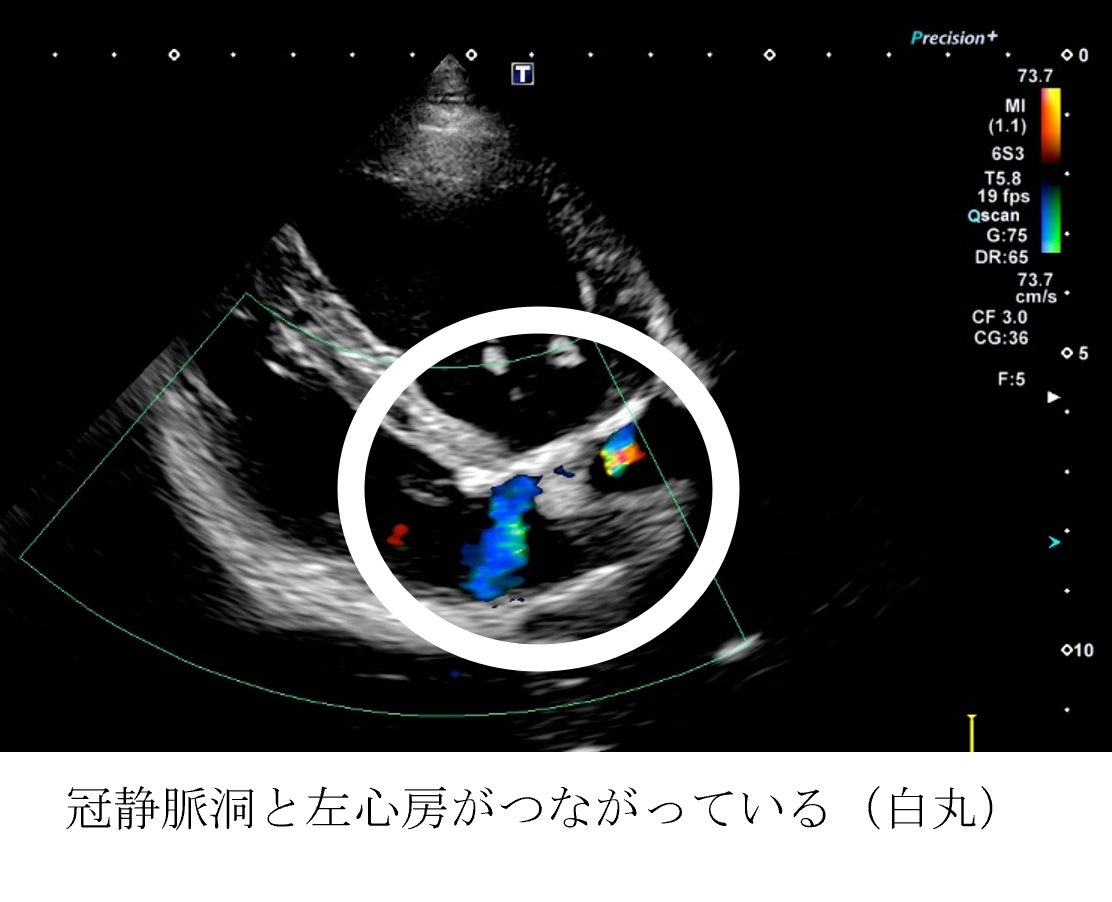

各種検査より、冠静脈洞左房交通症と診断しました。